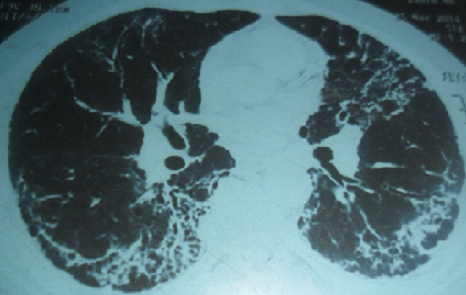

Le syndrome des antisynthétases correspond à l'association d'une myosite, une polyarthrite, un phénomène de Raynaud, une atteinte pulmonaire interstitielle et une hyperkératose fissurée des mains. Des anticorps de type «antisynthétases», en particulier l'anticorps anti-Jo1caractérise ce syndrome. L'atteinte cardiaque est rare, pouvant être parfois fatale. Patient âgé de 42 ans, hospitalisé pour des myalgies diffuses évoluant depuis un mois, une polyarthrite des genoux et des poignets, une dyspnée récente et un phénomène de Raynaud. L'examen physique a révélé une tachycardie sinusale à 110 battements /minute, un déficit musculaire prédominant aux ceintures, une hyperkératose fissurée des paumes des mains et des râles sous crépitants aux deux bases pulmonaires. L'examen biologique a montré un taux élevé des enzymes musculaires à 5 fois la normale, un syndrome inflammatoire, un bilan hépatique et rénal sans anomalies. L'électromyogramme a confirmé un tracé de type myogène. Le bilan immunologique a révélé la présence d'anticorps anti-Jo1. Les explorations fonctionnelles respiratoires ont conclut à un syndrome restrictif sévère. Le scanner thoracique a retrouvé un aspect en rayon de miel évocateur d'une fibrose pulmonaire. Un syndrome des antisynthétases a été évoqué. Le traitement s'est basé sur une corticothérapie associée aux boli de cyclophosphamide. L'évolution était marquée par l'amélioration des signes musculaires et articulaires. Devant la persistance de la tachycardie inexpliquée et l'aggravation de la dyspnée, des explorations cardiaques ont été réalisées montrant une myocardite compliquée d'une insuffisance cardiaque sévère. Le patient était rapidement décédé dans un tableau de défaillance cardiaque compliqué d'un état de choc.